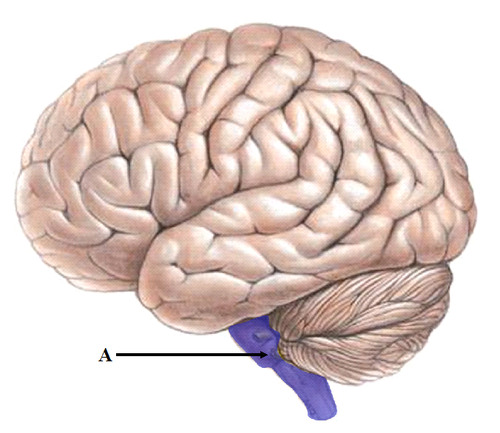

brainstem (def)

the oldest part and

central core of the brain, beginning

where the spinal cord swells as it

enters the skull; the ____________ is

responsible for automatic survival

functions.

central core of the brain, beginning

where the spinal cord swells as it

enters the skull; the ____________ is

responsible for automatic survival

functions.

12

New cards

brainstem (pic)